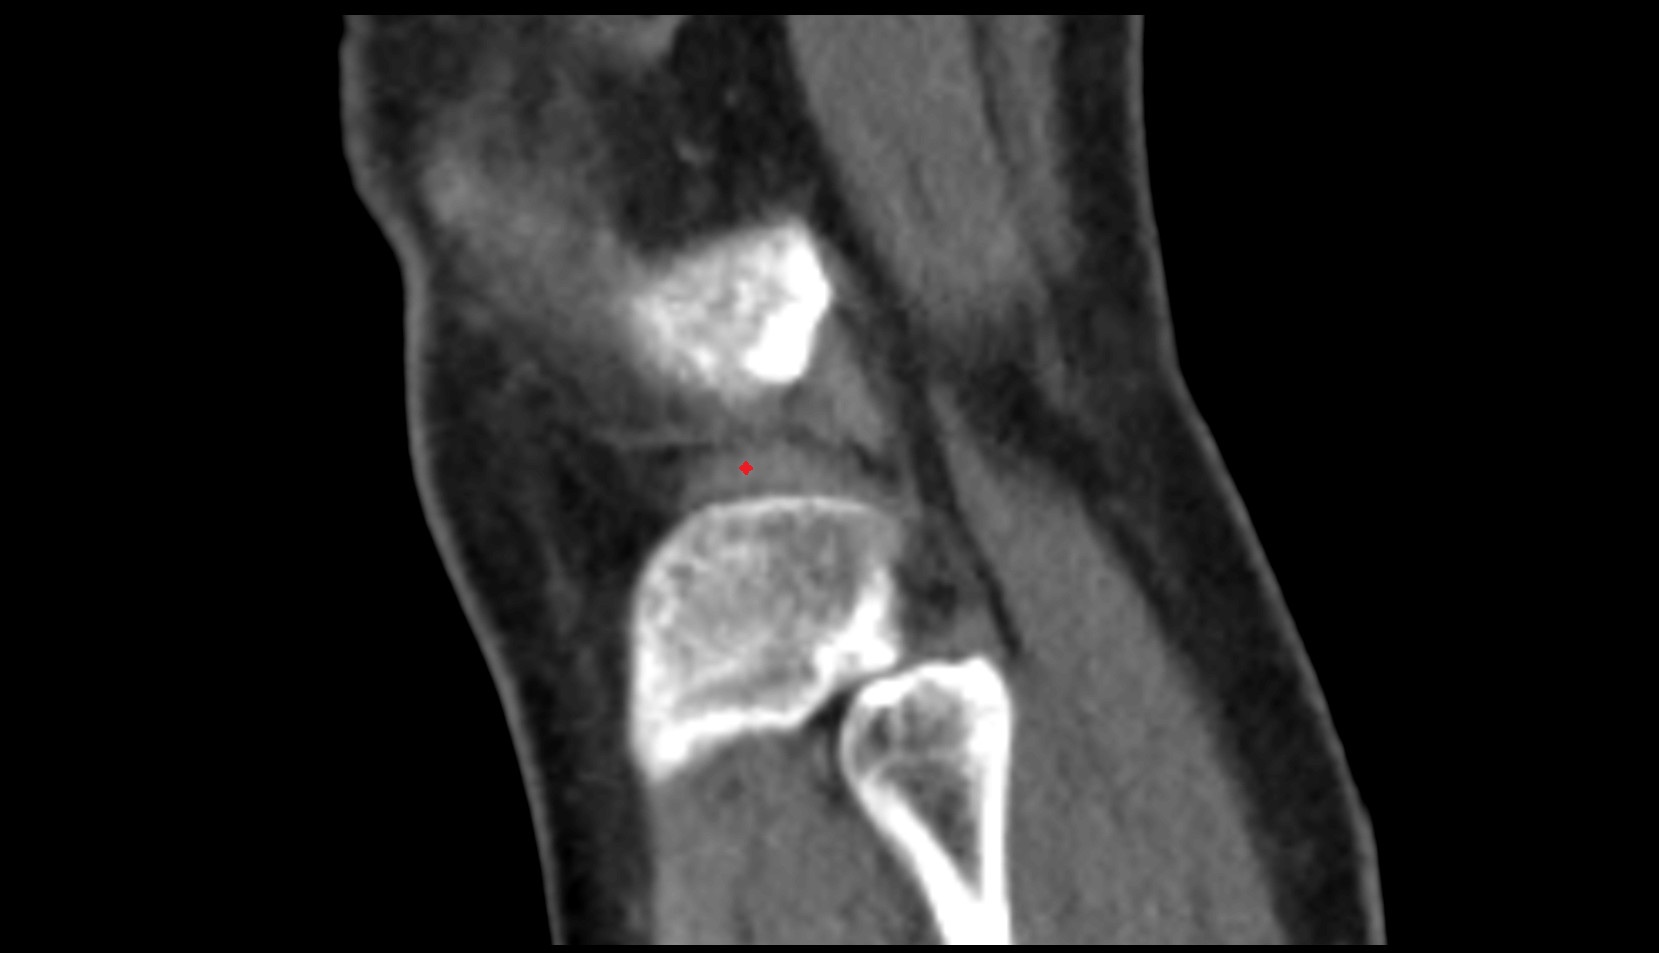

- Knee Joint

- Patella

- Infrapatellar fat pad

- Patellar tendon (patellar ligament)